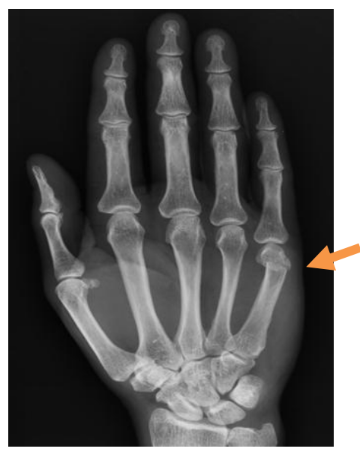

What is a hand (5th metacarpal neck) fracture?

You have a minor break near the knuckle and it will usually settle in three weeks.